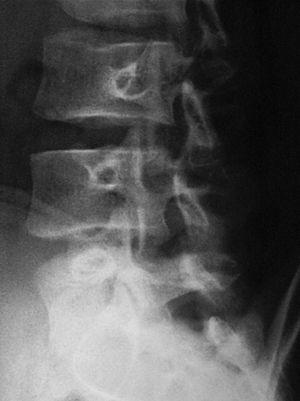

El nou estudi radiogràfic demostra espondilòlisi L5 dreta i persistència d'integritat de l'hemiarc esquerre (figs. 5 i 6). Igualment, l'estudi radiogràfic dinàmic demostra estabilitat completa de l'articulació lumbosacra (fig. 7). Per tot això es planteja l'alta esportiva, per bé que es recomana de continuar un mes més el tractament, i ajornar la tornada a la pràctica esportiva.

Figura 5

Figura 6

Figura 7